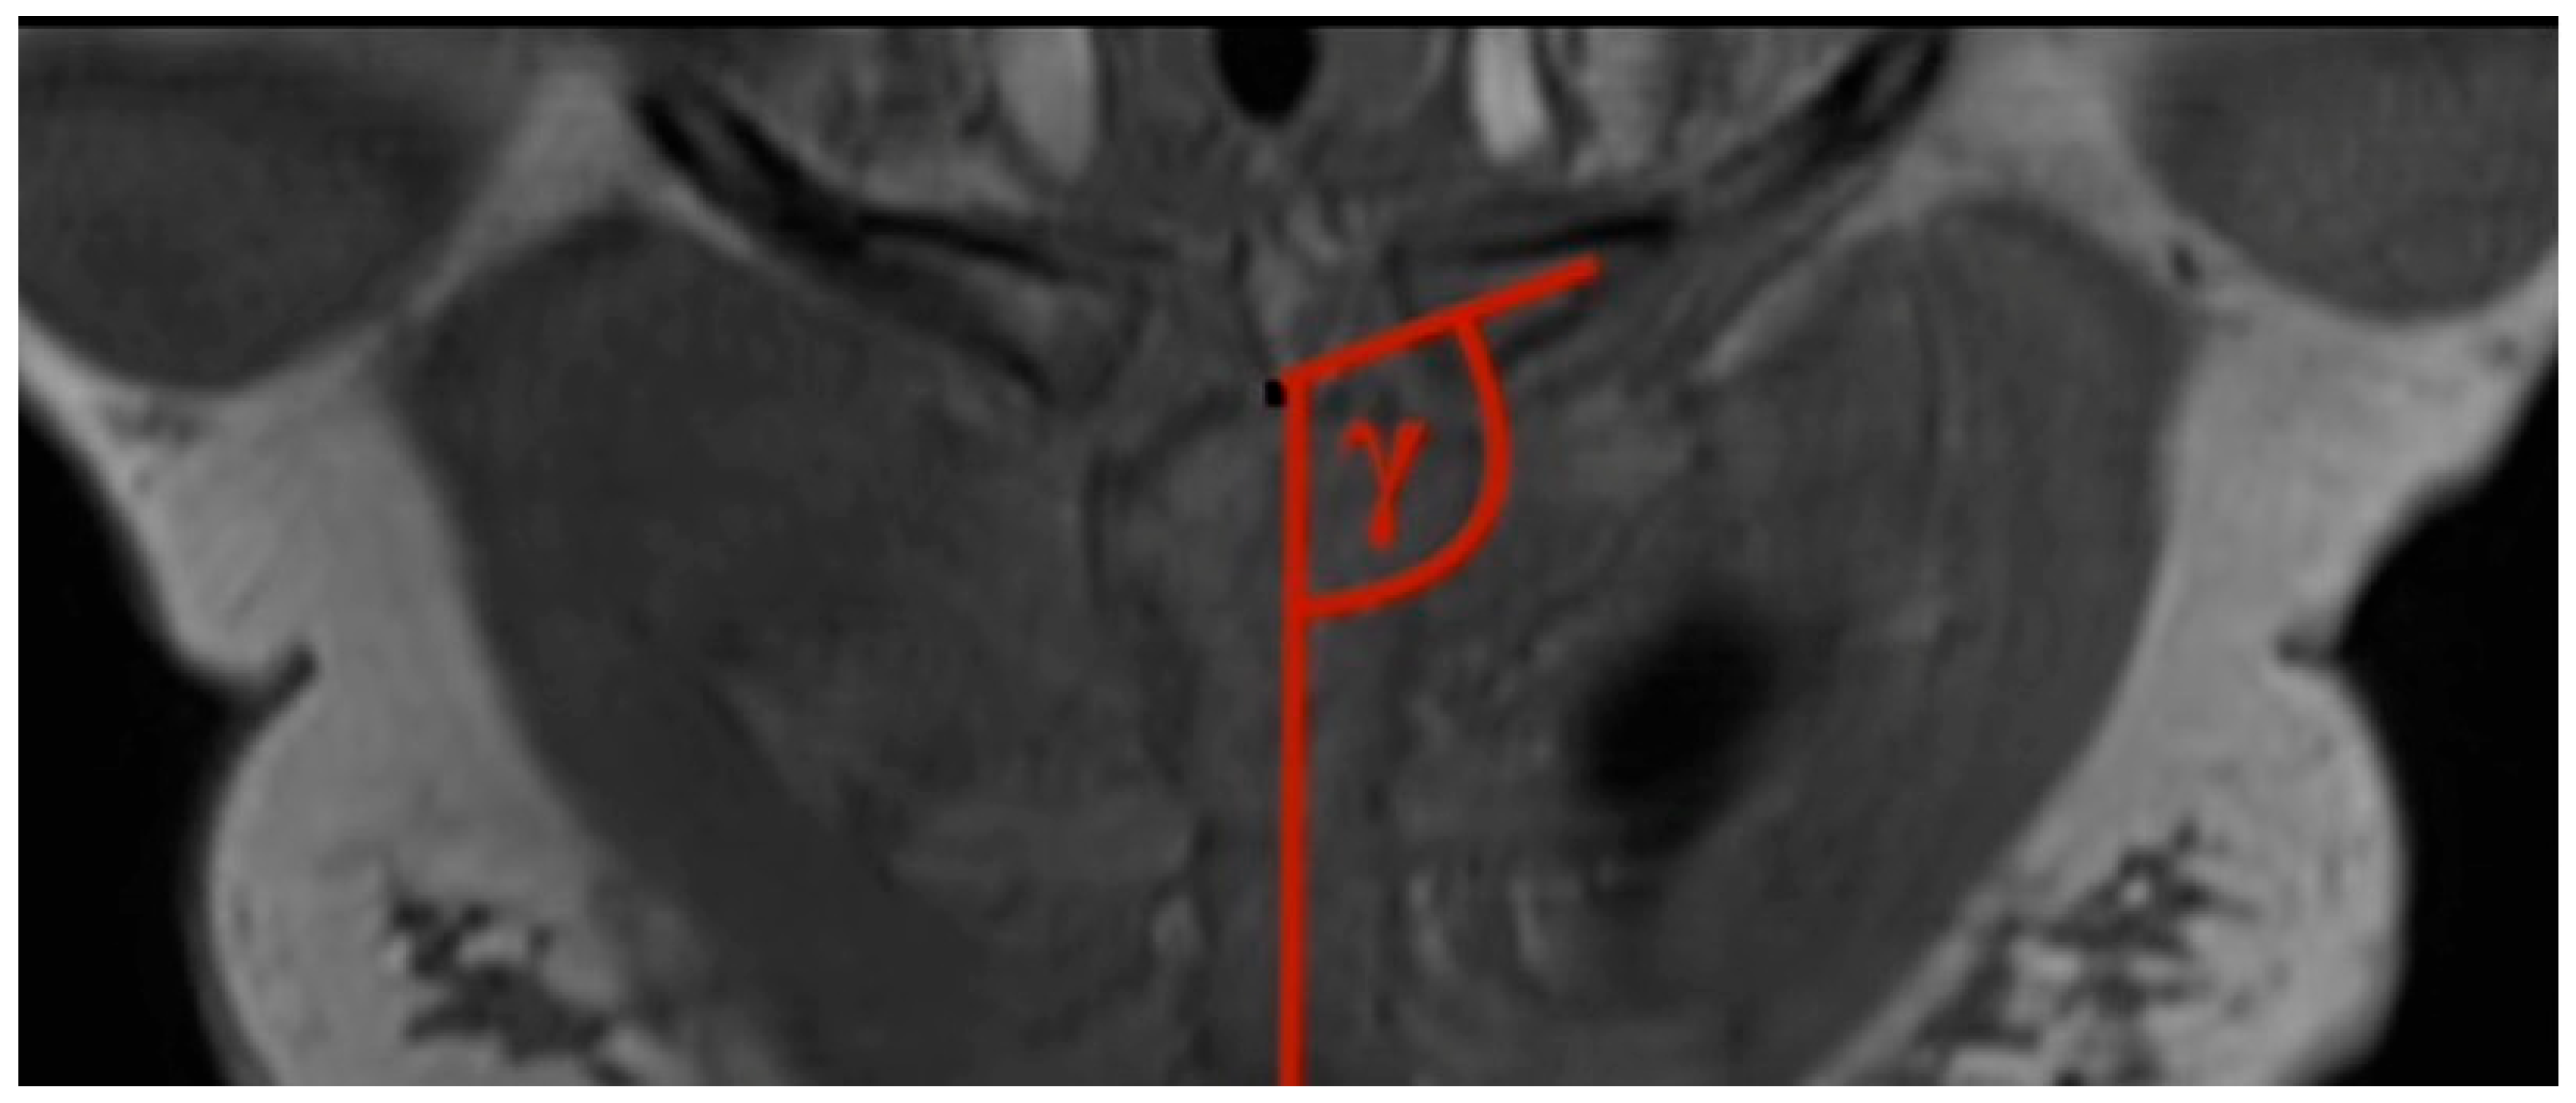

- Clavicular–sternal angle: The lengthwise axis of the clavicle is determined by a line, which is drawn from the middle of the lateral clavicle to the middle of the medial clavicle. The vertical axis of the sternum is drawn from the middle of the cranial end of the sternum to the xiphoid process of the sternum. Those two axes created the obtuse angle gamma (Figure 3).